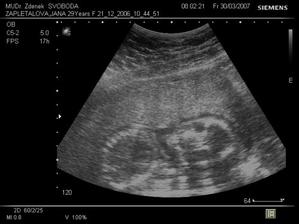

Tomášek

Tomášek se narodil přesně 3 týdny před termínem v Plzni na Slovanech 30.7.2007 Měřil 50 cm a vážil 2900g